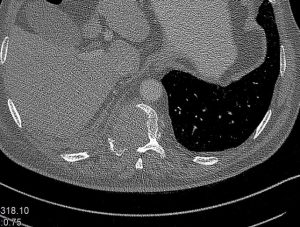

Ασθενής άνδρας 72 ετών με έντονη ραχιαλγία και ιστορικό καρκίνου του πνεύμονα.

Ο απεικονιστικός έλεγχος με μαγνητική και αξονική τομογραφία της σπονδυλικής στήλης ανέδειξε μάζα κυρίως στο σώμα του 10ου θωρακικού σπονδύλου (Θ10) με περιβρογχισμό και πίεση επί του νωτιαίου μυελού. (Σημειώστε και τη διήθηση του Θ9 σπονδύλου, χωρίς οστεόλυση).